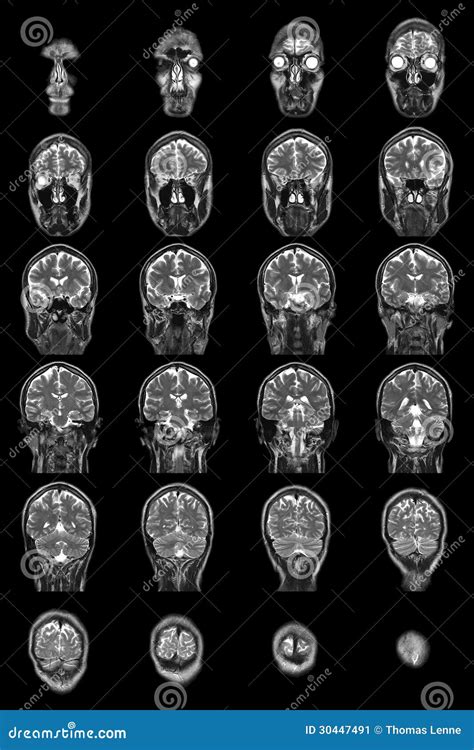

• normal brain mri coronal

• normal brain mri radiopaedia

• normal brain mri axial

• normal brain mri t2